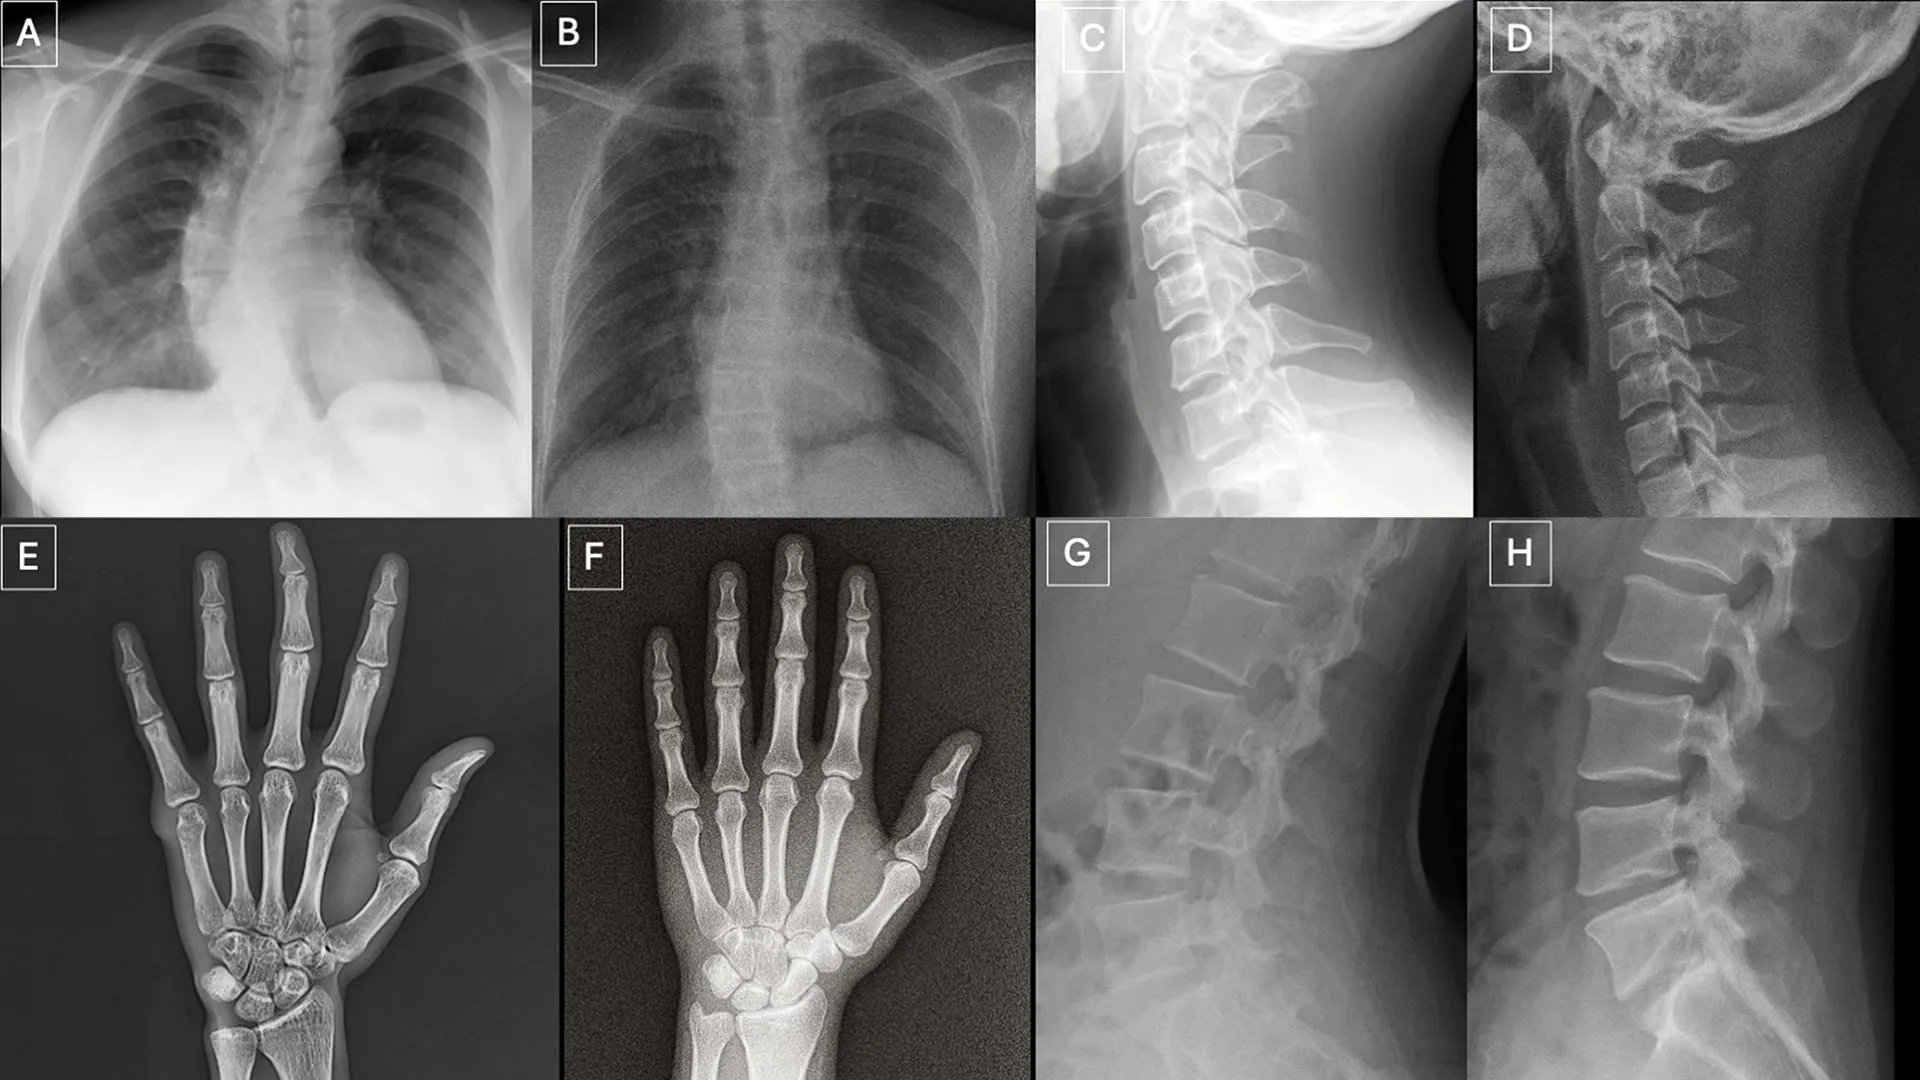

Um novo estudo publicado em 24 de março na Radiology, o jornal da Sociedade Radiológica da América do Norte (RSNA), …